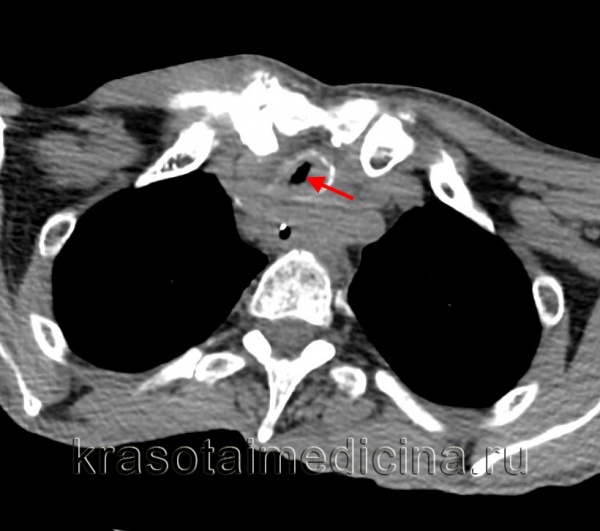

КТ органов грудной клетки. Выраженный стеноз проксимальных отделов трахеи вследствие вторичного распространения опухоли гортани